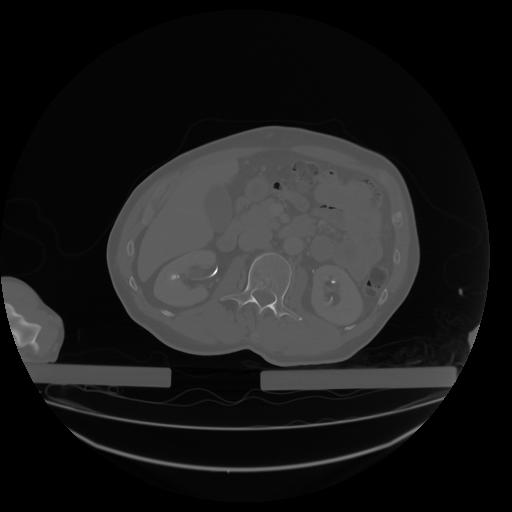

27 CUERPO,CE,Axial,3.0,CUERPO,,